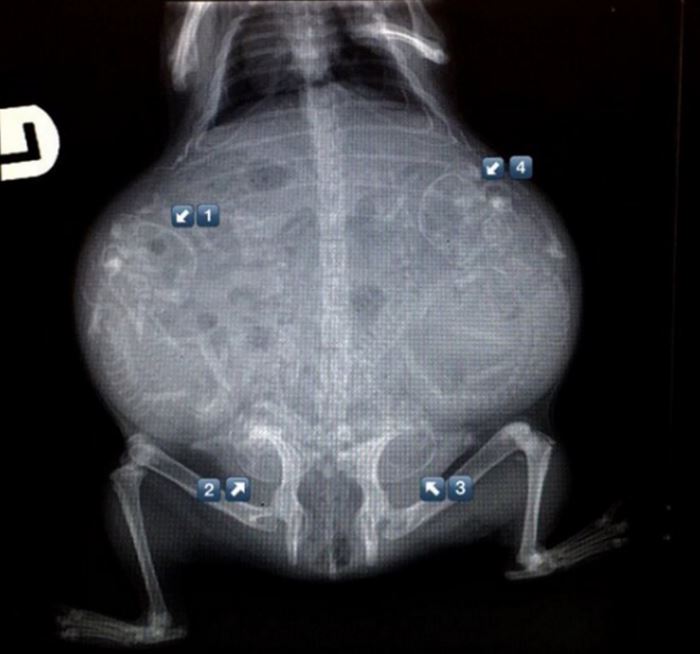

Guinea Pig x-ray of pregnant Teddy | my pigs | Pinterest | Pigs and …